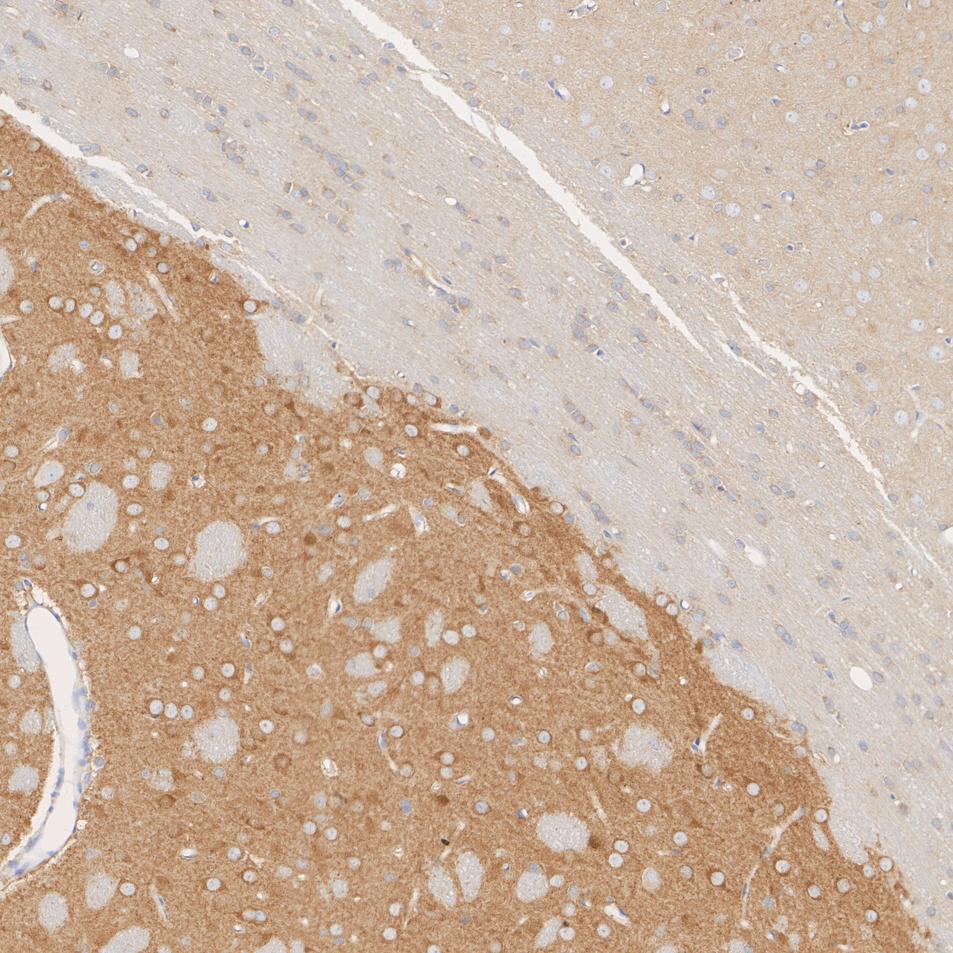

Gephyrin Recombinant Rabbit Monoclonal Antibody [JG34-47]

IHC-P